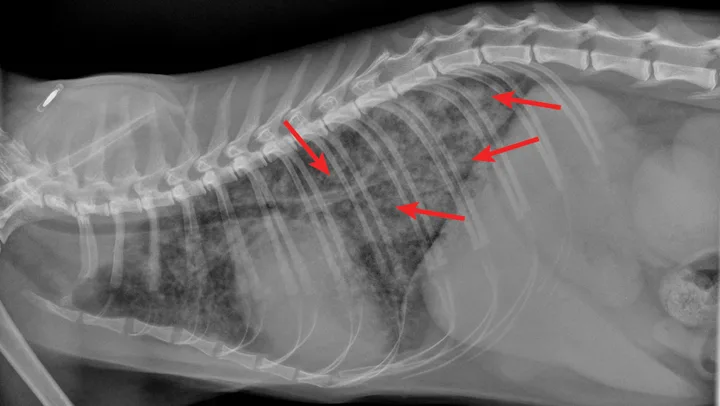

Overt cardiomegaly may be understated on radiographs because of changes in internal diameter that do not affect the overall cardiac silhouette. Vertebral heart score >9.3 supports a CHF diagnosis.1 Pulmonary venous congestion can be absent, and pulmonary arterial distension may be appreciated. The presence of pleural effusion with simultaneous pulmonary infiltrates is supportive of CHF (Figure 1).2

Congestive heart failure. Note the pleural effusion (arrows).